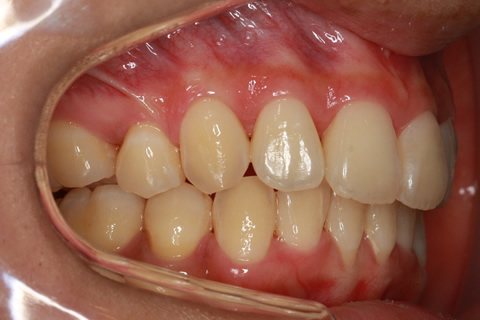

ハーフリンガル矯正3:上の歯のみ舌側矯正で治療(矯正期間24ヶ月)

治療前

治療中(開始直後)

治療中(開始半年後)

治療後

- 年齢・性別

- 25歳女性

- 治療期間

- 2年0ヶ月

- 抜歯

- 上下4番抜歯

- 治療費

- 110万円

- 治療内容

- 表側矯正と比較して、力学的な操作性が複雑なため、ボーイングエフェクトを起こしやすい。